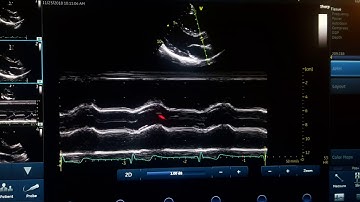

M mode concepts